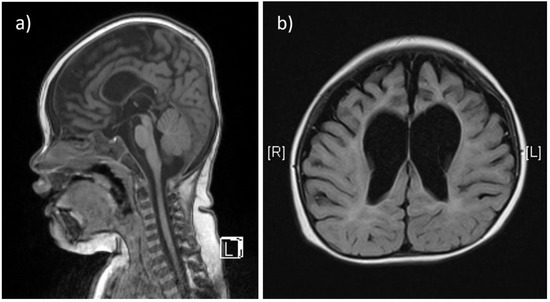

Two affected patients were born to healthy, non-consanguineous parents of Chinese descent. The first child (Patient 1) was a baby girl, born at 41 weeks of gestation by vaginal delivery, weighing 3300 g at birth. Prenatal exams were smooth, and the pregnancy was uneventful. She exhibited poor locomotive abilities a few months after birth, and had to rely on a nasogastric tube for feeding until 12 months. Staying floppy, she was unable to roll over, and exhibited progressive hypotonia and hyporeflexia in the extremities. Frequent generalized tonic-clonic seizure episodes (about every 1.5 h) were detected after 12 months, and she showed signs of further neurodegeneration since the onset of seizure episodes (stopped smiling and sucking, and lacked visual attention). She could make sounds without forming words. An X-ray revealed severe scoliosis and advanced bone age, more than 2 years older than chronological age. Brain MRI at 11 months showed thinning of the corpus callosum, diffuse cerebral atrophy involving both gray and white matters, and sulcal widening with prominent enlargement of the ventricular systems (Figure 1a,b). Other clinical exams showed thrombocytopenia and the presence of accessory spleen. Karyotyping analysis yielded normal results. She had recurrent respiratory infections and died of respiratory failure at 3 years of age.

Figure 1.

The T1-weighted, sagittal section of brain MRI from patient 1 shows thinning of the corpus callosum (a). The T2-weighted, axial section from the same patient shows diffuse cerebral atrophy involving both gray and white matters, and sulcal widening with prominent enlargement of the ventricular systems, especially at the frontal horns (b).